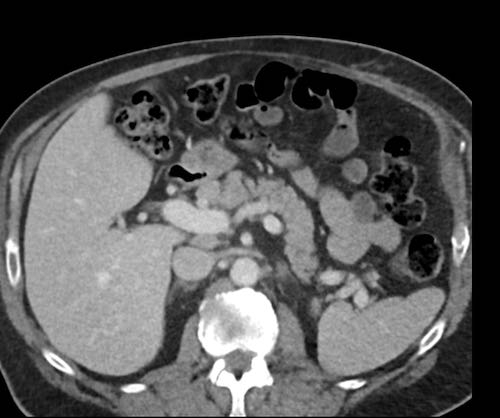

Cuộn xem ảnh CT

Ca lâm sàng 1

Cuộn qua các lát cắt.

Bạn có thể phát hiện tất cả các tổn thương cấy ghép phúc mạc không?

Bệnh nhân này đã được phẫu thuật và toàn bộ phúc mạc được ghi nhận phủ kín bởi các tổn thương u dạng kê.